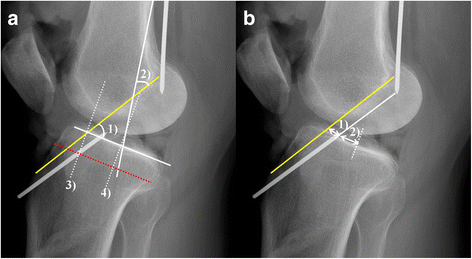

Blumensaat Line. On a normal radiograph, the line intersects the inferior pole of the patella , and so can be useful in diagnosing a broken femur as well as a patellar tendon rupture. Blumensaat line, also known as the intercondylar line, is the line drawn along the roof of the intercondylar notch of the femur on a sagittal view of the knee. Blumensaat's line is a line which corresponds to the roof of the intercondylar fossa of femur as seen on a lateral radiograph of the knee joint. Blumensaat line is important because the angle that it forms on the radiograph with various other lines can be used to determine the position of the patella. Blumensaat line is a line which corresponds to the roof of the intercondylar fossa of the femur as seen on a lateral radiograph of the knee joint. The blumensaat line has been suggested as an indication of the relative position of the patella; The angle at which this line appears on the radiograph can be used to determine the position of the patella or diagnose an acl injury. Blumensaat's line is a line which corresponds to the roof of the intercondylar fossa of femur as seen on a lateral radiograph of the knee joint. However, too much variation is introduced by knee flexion, angle of the blumensaat line with the femur, vertical length of the patella, and depth of the intercondylar notch for this method to be useful. Blumensaat's line is a line which corresponds to the roof of the intercondylar fossa of femur as seen on a lateral radiograph of the knee joint. On a normal radiograph, the line intersects the inferior pole of the patella, and so can be useful in diagnosing a broken femur as well as a patellar tendon rupture. The blumensaat line (bl), a radiographic landmark representing the roof of the intercondylar fossa, will accurately approximate the native acl (nacl) length and may aid in the prevention of gtm. It can be used for: Intercondylar line, blumensaat's line definition of blumnesaat line it is the tangent drawn along the roof of intercondylar notch or fossa of the… morphologic variations of blumensaat line (iriuchishima's classification). Blumensaat line — a linear shadow on the lateral radiograph of the knee, representing tangential bone in the intercondylar space.